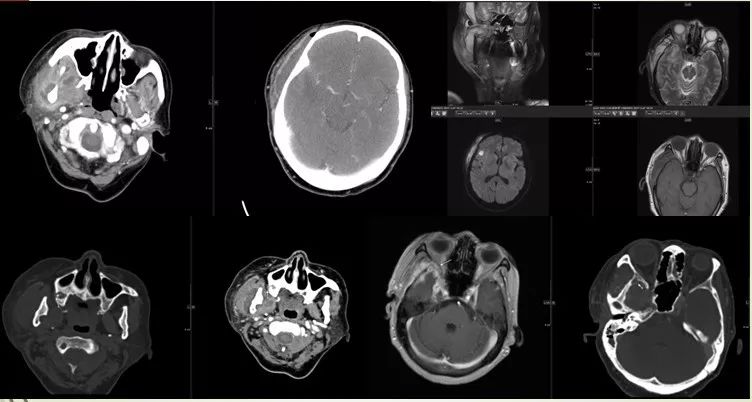

9 腮腺间隙、咽旁间隙

女,16岁,发现左侧颈部肿物7日余。

鳃裂囊肿并感染。

10 下颌下间隙

女,20岁,1个月前无意间发现右侧颈上部有一肿物,约鸡蛋样大小,触摸时质硬软,稍有疼痛。

11 颊间隙、下唇部

男,19岁,3周前自觉左面部肿痛不适,肿痛区可见一约“黄豆粒”样大小的肿物,按压时疼痛加重,至当地医院应用“消炎药” 治疗无明显疗效,肿痛症状加重,肿物逐渐增大。

表皮样囊肿并感染。

12 眶下间隙、颊间隙、咀嚼肌间隙、咽旁间隙

男,61岁,左侧面颊部、颌下、颏下肿胀15天,表面皮肤稍红,皮温不高,未扪及明显波动感。

角化囊肿并感染。

13 翼颌间隙、咽旁间隙

左下阻生齿拔除术后10天,伴吞咽疼痛4天。

手术导致的翼颌间隙及咽旁间隙脓肿形成。

14 眶下间隙、颊间隙

42M,10天前发现左侧上唇部有一“粉刺”,开始为红色硬结,用手按压患处,后形成黄白色脓头,8天前左侧上唇肿胀、疼痛,局部破溃溢脓,伴同侧眶下肿胀,发热,体温38℃。

唇痈伴发蜂窝织炎,局部脓肿形成。